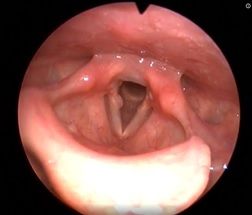

Рис 2А. Двусторонний паралич гортани. До операции.

Рис 2Б Двусторонний паралич гортани. 7 сутки после операции

Рис 2В Двусторонний паралич гортани. 1 месяц после операции